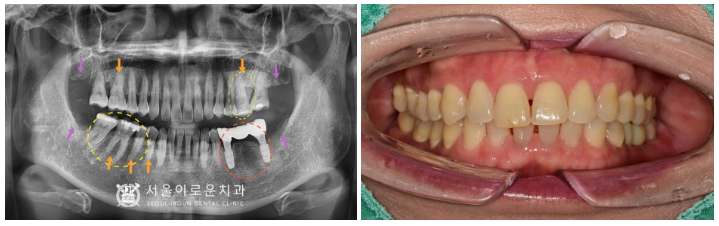

정밀한 검사를 위해

파노라마 사진을 촬영해 보았더니,

제일 불편감을 호소하셨던

빨간 동그라미 표시의

왼쪽 아래 어금니(#35,37) 부위는

기존 브릿지 보철물이

수복 되어 있는 상태였습니다.

보철물 주변 잇몸뼈가

많이 흡수되어 있는 상태로

동요도가 2도 이상으로 많이 흔들려

안타깝게도 살려 쓰기에는 힘든 상황이라

발치 후 임플란트 식립을 계획하였습니다.

또한 보라색 화살표 부위의

사랑니가 4개 모두

맹출이 되어 있었는데요.

사랑니가 맨 안쪽에 위치해 있다 보니

위생관리가 잘되지 않고 있어

추후 다른 치아에까지

영향을 끼칠 것을 고려하여

사랑니 모두 발치를 진행하기로 하였습니다.

그리고 환.자분께서 내원 당시

찬물에 치아가

많이 시리다고 말씀해 주셨는데요.

확인해 보았더니 주황색 화살표 부위의

치아 허리 부분에 해당하는

치경부가 많이 닳아 있는

치경부마모증이 있었습니다.

마지막으로

노란색 동그라미 표시의 치아들엔

우식이 발견되었는데요.

왼쪽 위 첫 번째 큰 어금니(#26)와

오른쪽 아래 큰 어금니 두 개(#46,47)는

기존 아말감 파절로

기존 충전물이 일부 파절되면서

주변으로 2차 우식이 관찰되었습니다.

또한 오른쪽 아래 두 번째 작은 어금니(#45)는

치.아 원심면에 우식이 보였습니다.

✅ 전 > 후 ✅

(2023.02.02ㅡ>2023.07.15)